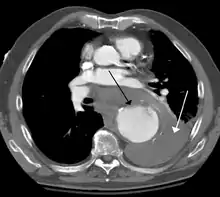

A thoracic aortic aneurysm is an aortic aneurysm that presents primarily in the thorax.

A thoracic aortic aneurysm is the "ballooning" of the upper aspect of the aorta, above the diaphragm. Untreated or unrecognized they can be fatal due to dissection or "popping" of the aneurysm leading to nearly instant death. Thoracic aneurysms are less common than an abdominal aortic aneurysm.[2] However, a syphilitic aneurysm is more likely to be a thoracic aortic aneurysm than an abdominal aortic aneurysm. This condition is commonly treated via a specialized multidisciplinary approach with both vascular surgeons and cardiac surgeons.

Diagnosis

Thoracic aortic aneurysm is defined as a cross-sectional diameter exceeding the following cutoff:

- 4.5 cm in the United States[8]

- 4.0 cm in South Korea[9]

A diameter of 3.5 cm is generally considered dilated.[8] However, average values vary with age and size of the reference population, as well as different segments of the aorta.